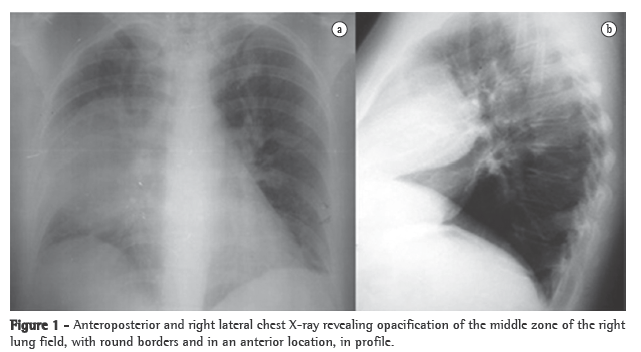

Complementary tests performed in the emergency room revealed normocytic normochromic anemia (hemoglobin, 11.3 mg/dL; mean globular volume, 86.8 fl; and mean corpuscular hemoglobin, 33.7 mg/L), normal total leukocyte counts (7 g/L), hypokalemia (3.3 mmol/L) and hypoalbuminemia (3 g/dL), as well as an increase in the levels of aspartate aminotransferase (60 U/L), alanine aminotransferase (79 U/L), lactate dehydrogenase (196 U/L), alkaline phosphatase (272 U/L) and C-reactive protein (19.2 mg/dL). The patient also presented hypoxemia on room air (PaO2: 79.5 mmHg) and mild hypocapnia (33 mmHg). A chest X-ray revealed opacity in the middle third of the right lung field (Figure 1).

Another chest X-ray, performed on postadmission day 8, showed that the opacity described above persisted. Subsequently, a CT scan of the chest, performed to clarify this issue, revealed a solid formation in the anterior mediastinum. The formation measured 10 cm in its largest diameter and maintained cleavage planes with the heart and the lung, as well as insinuating itself between the lung lobes and compressing them. In addition, a magnetic resonance imaging scan was performed to determine the true extent of the lesion, especially in terms of the cleavage plane with the mediastinal structures (Figure 2), and the findings confirmed those of the CT images.